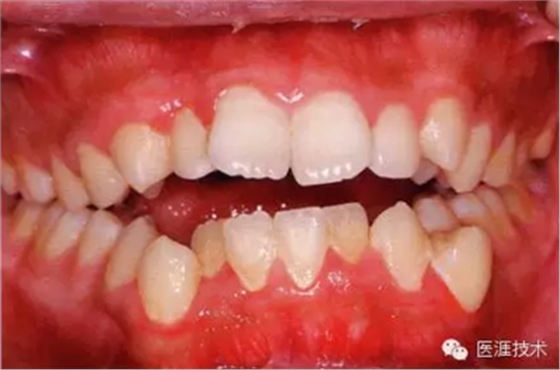

28歲女性的健康口腔內(nèi)部

圖為28歲女性,無特殊全身疾病,不抽煙。10年前來院就診保養(yǎng)3年,期間中斷過,現(xiàn)又開始。齲壞風險高,當初初診時已有好幾顆牙的鄰面有填充物,再填充了3牙的鄰面齲,現(xiàn)牙周組織健康。